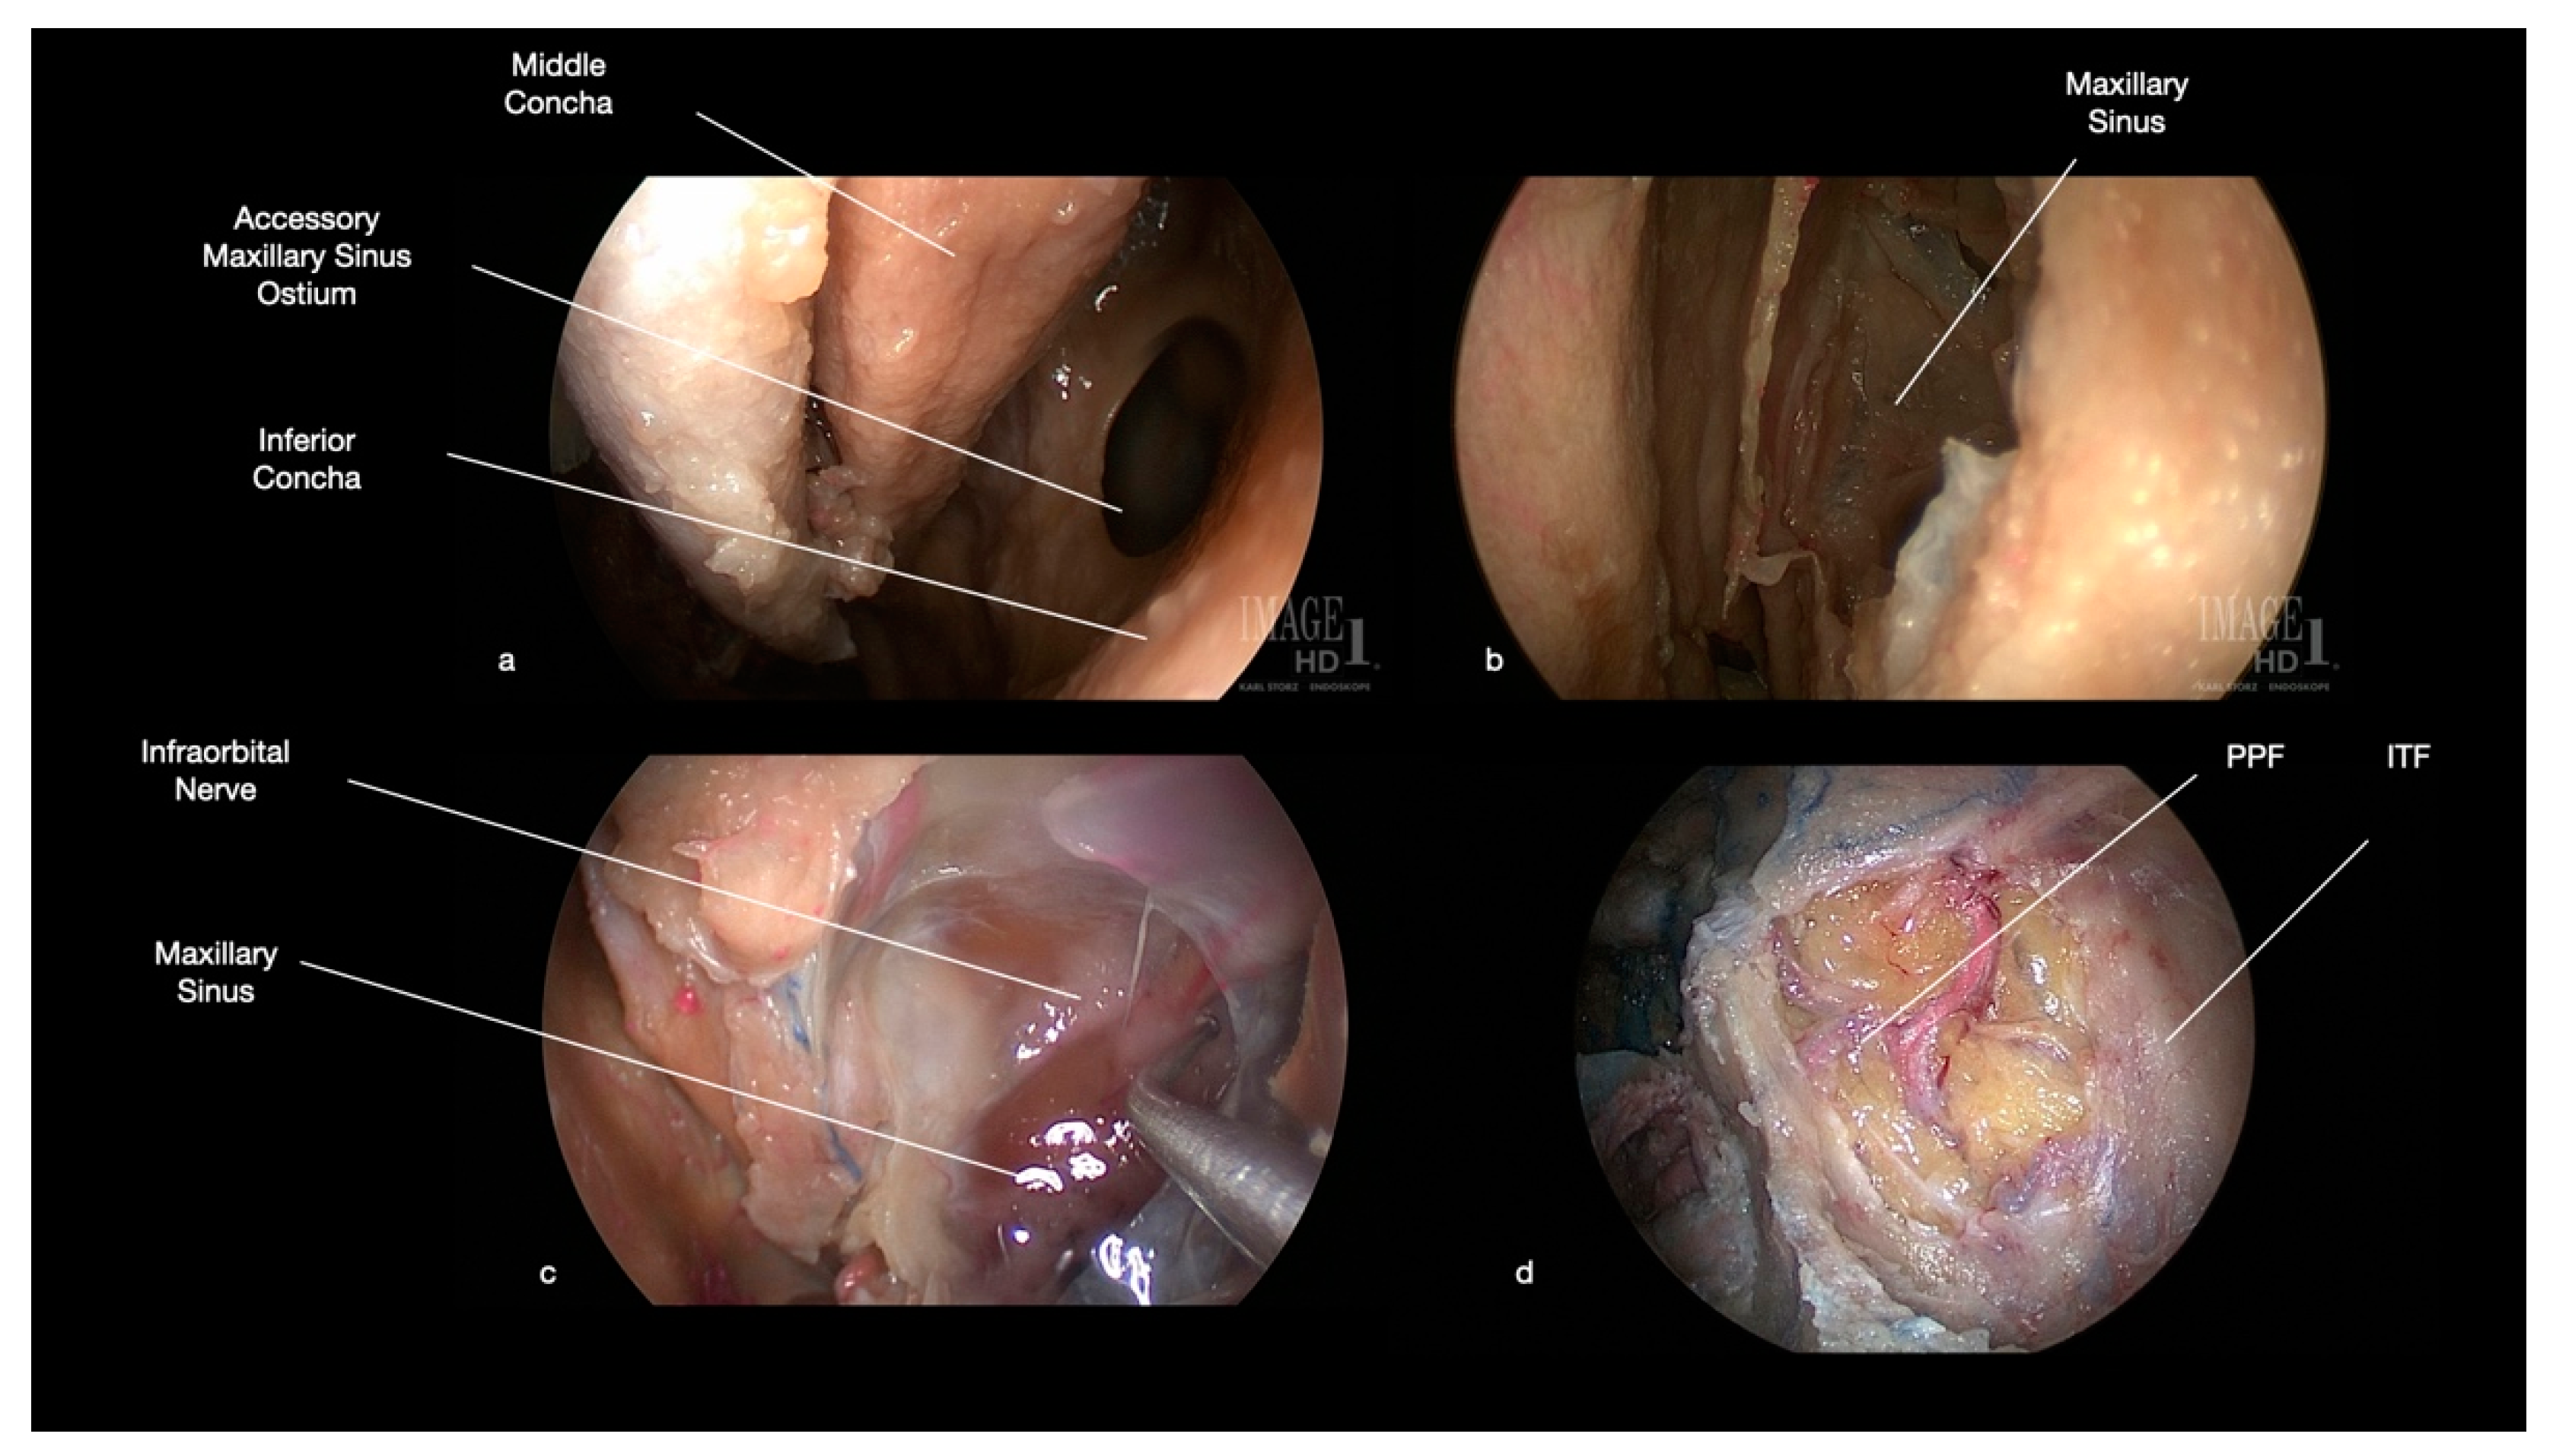

7. Endoscopic Endonasal Approach to Tumors of Infratemporal and Pterygopalatine Fossae